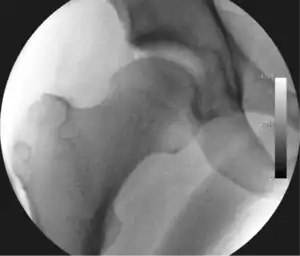

Figure 4. A needle is passed into the joint, breaking the 'suction seal', and allowing further distraction of the hip joint with minimal extra traction

The next step is to insert a fine needle under x-ray guidance into the hip joint. This breaks the 'suction seal' of the joint and allows further distraction if necessary (see fig 4). The surgeon wishes to see the ball move out the socket by approximately 1 cm, so that access to the hip joint can be achieved with minimal risk of damage to the joint surfaces. Most surgeons will inject fluid into the joint at this stage, again to ensure that there is enough space between the ball and socket for safe instrument access. This needle is then removed. The next step is placement of the 'portals', or the small holes made to pass instruments into the joint. This is achieved by again passing a fresh hollow needle into the joint under x-ray control, usually in a slightly different position. The reason for this is so the surgeon can ensure that the needle, and subsequent cannulae do not penetrate and damage the acetabular labrum or cartilage joint surfaces (see fig. 5). Again, surgeons will have their own preferences as to their preferred placement. Through this hollow needle, a long thin flexible guide wire is passed into the joint, and the needle is removed over it, leaving the guide wire in situ. A small cut in the skin is made around the wire, to allow for larger cannulae to be placed over the wire through the portal. The wire therefore guides the larger cannulae into the joint. The most common external diameters of cannulae used are between 4.5 and 5.5 mm. Once the surgeon is satisfied that the cannula is in the correct position, by a combination of feel and x-ray guidance, the guide wire can be withdrawn. Once the first portal is correctly placed, any further portals may be created once the camera is in position, to ensure that they are placed with minimal risk to the joint surfaces. This process can be repeated to gain as many points of entry to the hip joint as the surgeon requires, normally between two and four. Certain of these entry points will be used for the viewing arthroscope and others for operating instruments.